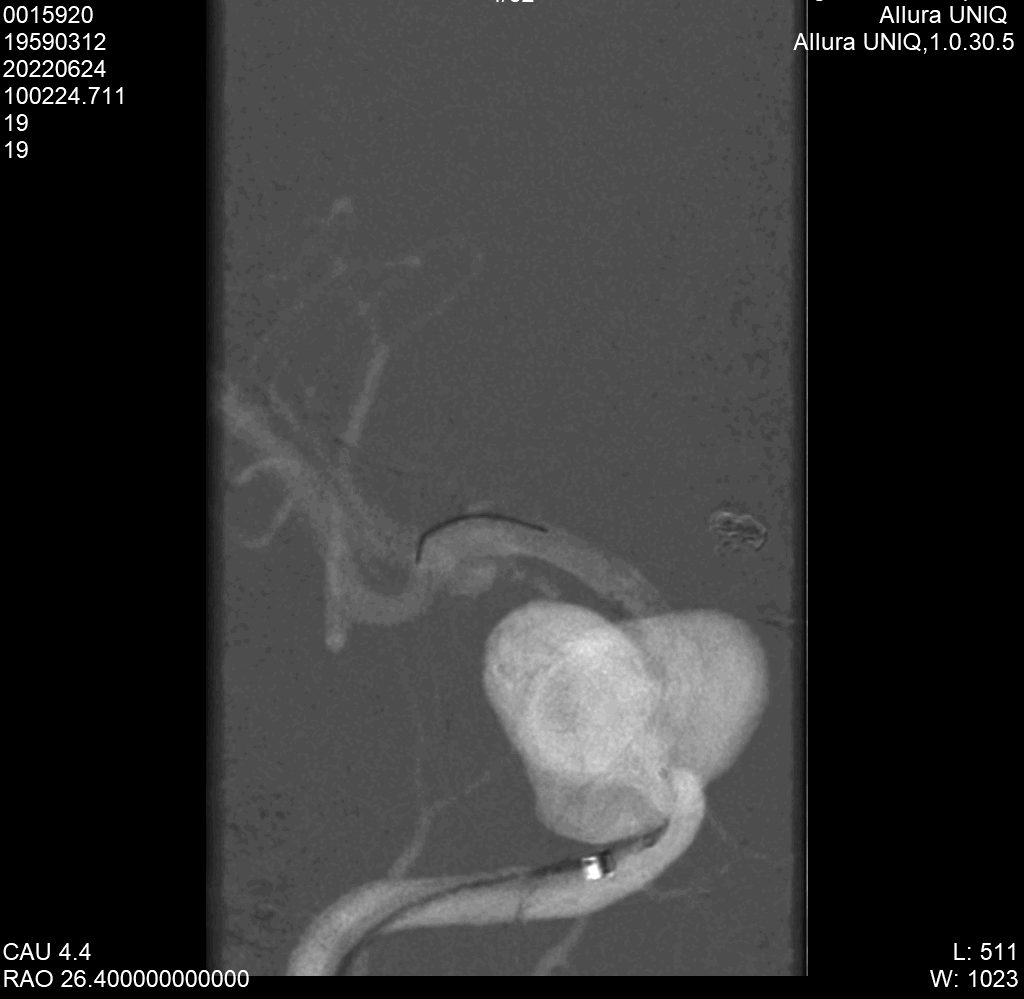

支架全部打开,定位满意,释放开关,解脱支架。

即刻造影显示血流重建,进入瘤腔明显减少。

填入2枚弹簧圈促进血栓形成。